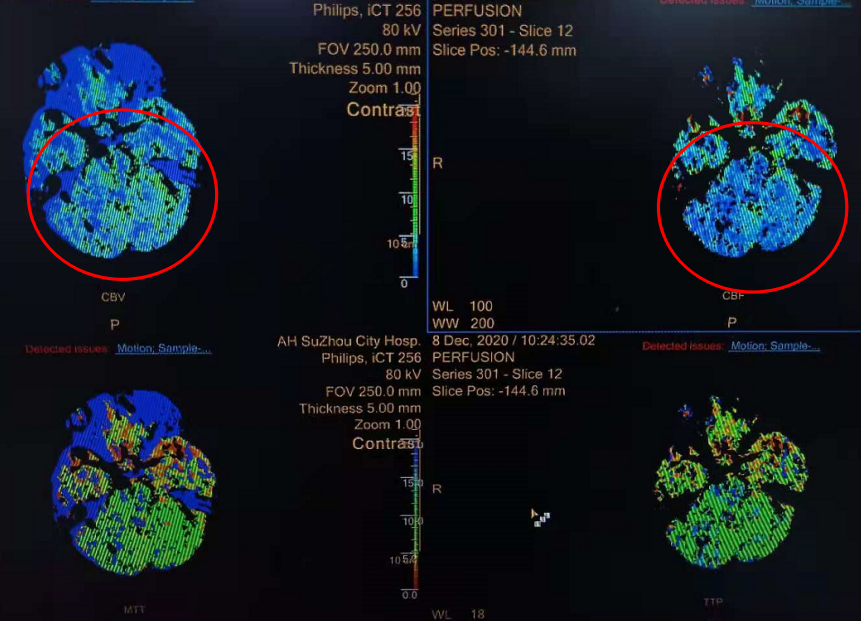

CTP提示:脑干及双侧小脑半球低灌注,CBF/CBV不匹配,存在缺血半暗带。